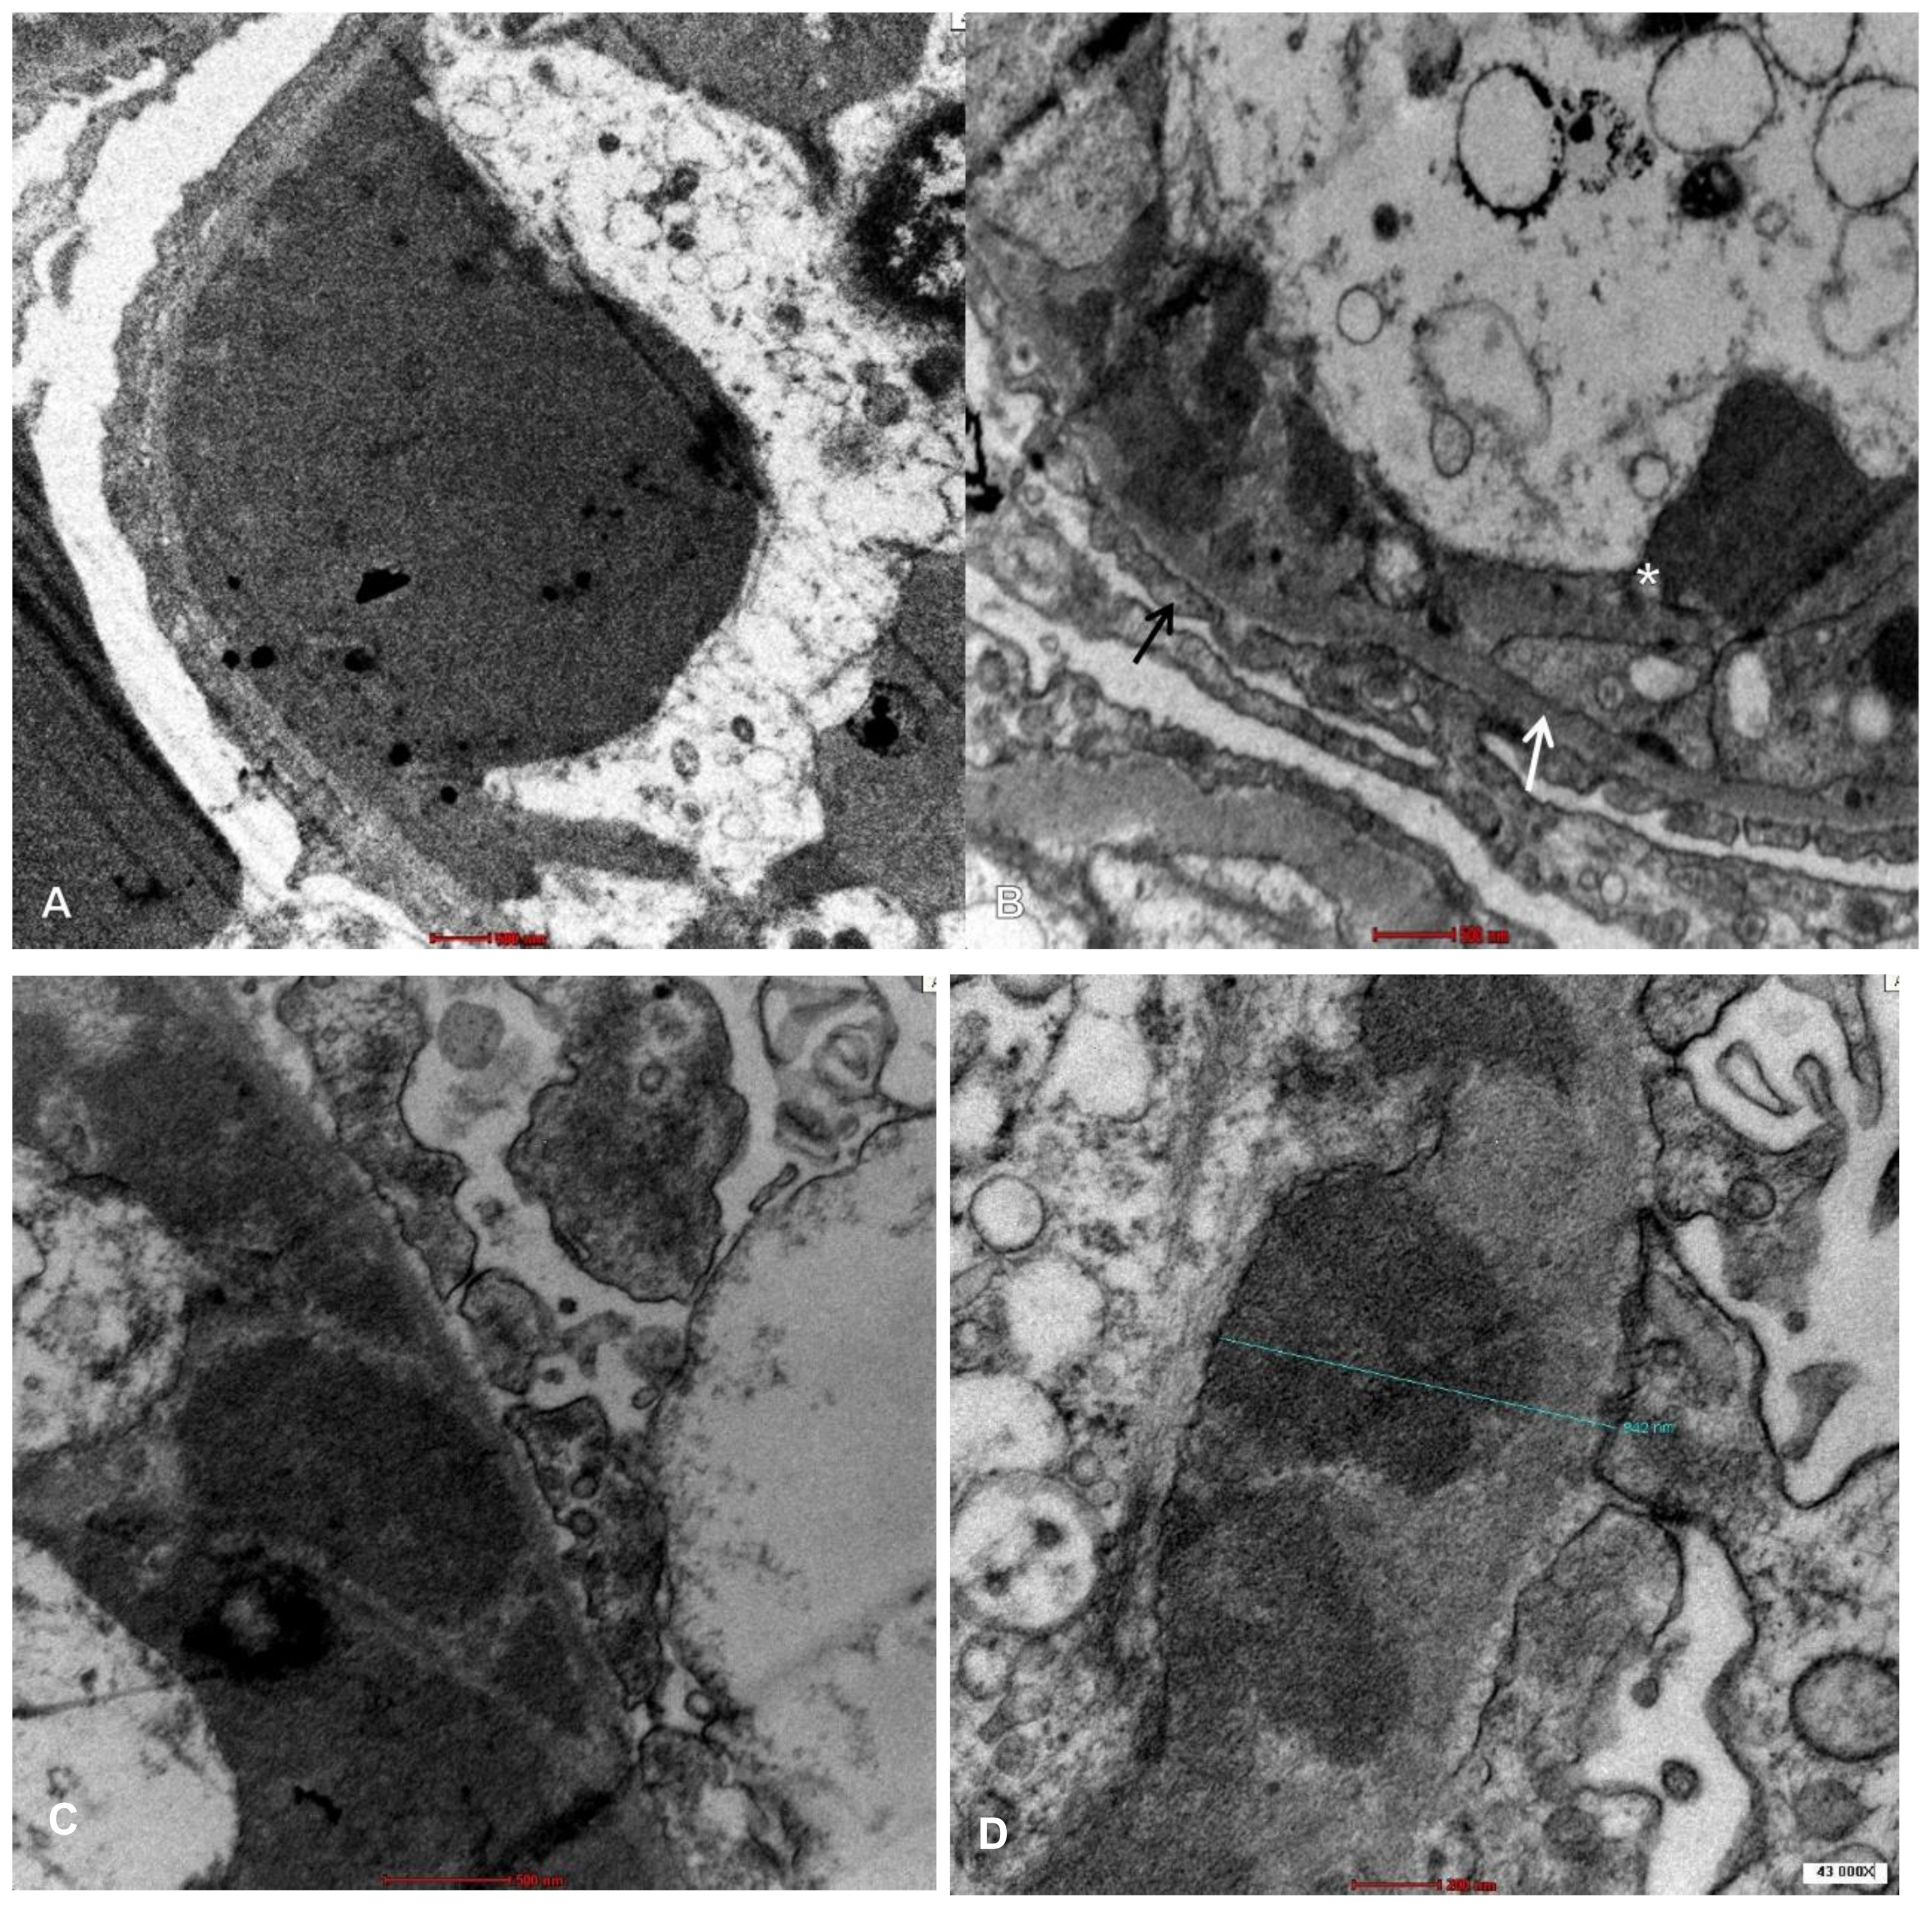

2. Case Presentation